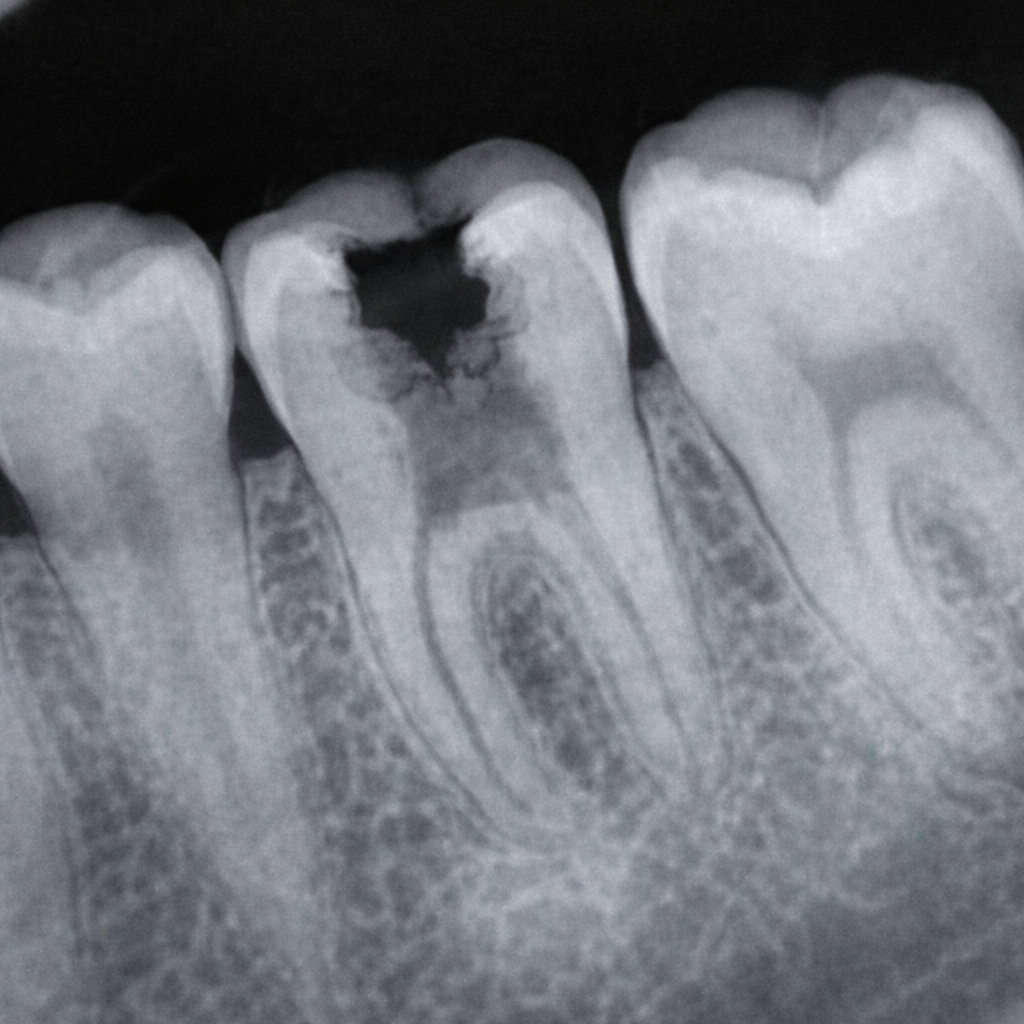

caries dental